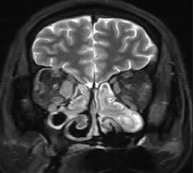

(3)眼眶增强核磁:可见右侧泪腺大于左侧,右侧内直肌明显增粗;结合既往检查,明确患者受累器官包括唾液腺、泪腺、淋巴结、鼻窦、肺、肝脏、泌尿系统、眼部等。

疗效反馈:治疗不足1个月时,患者喘息、眼睑肿胀、鼻塞流涕症状逐渐减轻至完全消失;激素减量至20mg/d时,鼻塞流涕症状轻度反复,但咳嗽胸闷未再发作;复查显示IgG4降至3.4g/L,IgE及嗜酸性粒细胞恢复正常;眼眶增强核磁提示增粗的内直肌明显缩小。